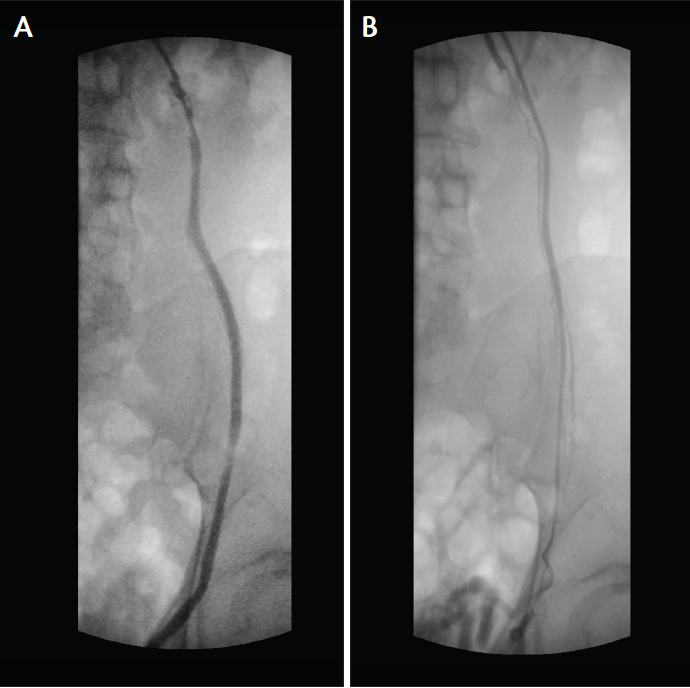

From www.researchgate.net

Transcatheter coil and glue embolization of recurrent varicocele after Coil Embolization Varicocele coils are commonly used embolic for varicocele, and both detachable and pushable coils can be used for. varicocele embolization is a minimally invasive method of treating varicoceles by embolizing the testicular. there are several options for the treatment of varicocele, including surgical repair either by open or. coils are the most commonly used embolic agents for. Coil Embolization Varicocele.